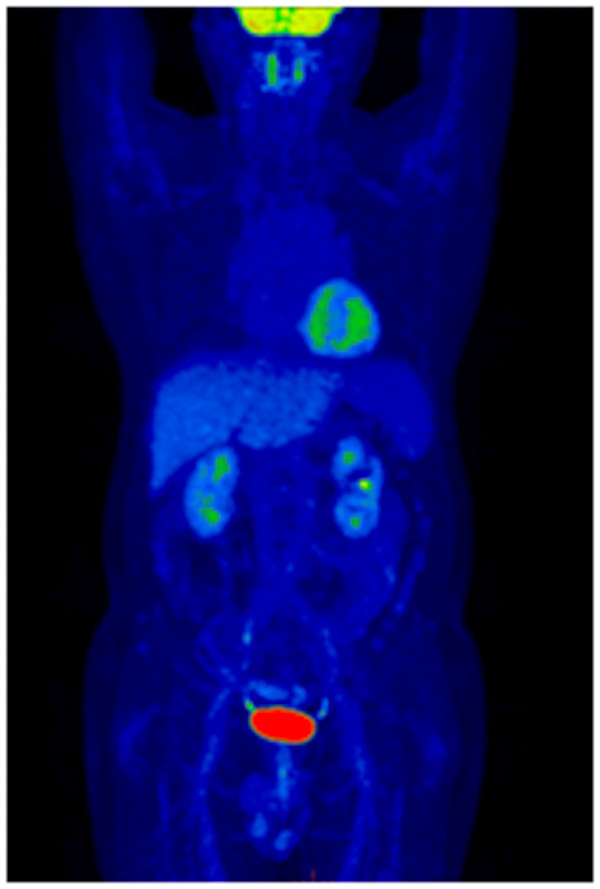

在PET-CT幫助黃先生找到所有淋巴瘤的病灶后,柳州市人民醫(yī)院血液內(nèi)科醫(yī)師們“對癥下藥”,患者經(jīng)過4周期化療后再次到核醫(yī)學(xué)科行PET-CT顯像。

治療后PET-CT顯像提示全身多發(fā)淋巴結(jié)較前明顯縮小、數(shù)量減少,部分可見低度腫瘤活性存在;兩側(cè)胸腔極少量積液,較前明顯吸收,取得了良好的療效。